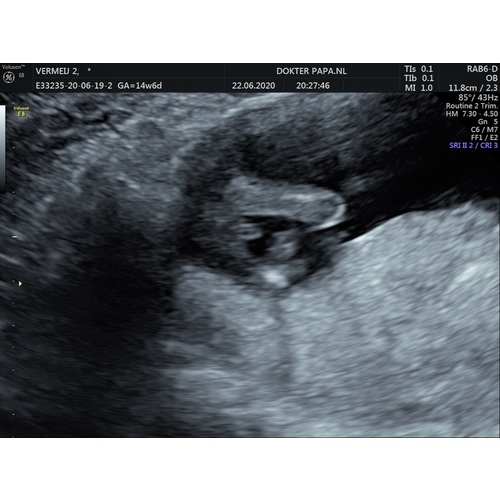

Nja ik wil mijn echo van gisteren ook nog wel delen. Zelf lag ik compleet dubbel hoe vriendlief de foto in handen kreeg.

We wisten het geslacht al met 13 weken. Zijn reactie was “nou nu weet ik zeker dat we een zoon krijgen, overduidelijk”

Hij begreep niet direct dat het piemeltje met het kleine pijltje word aangewezen 😂